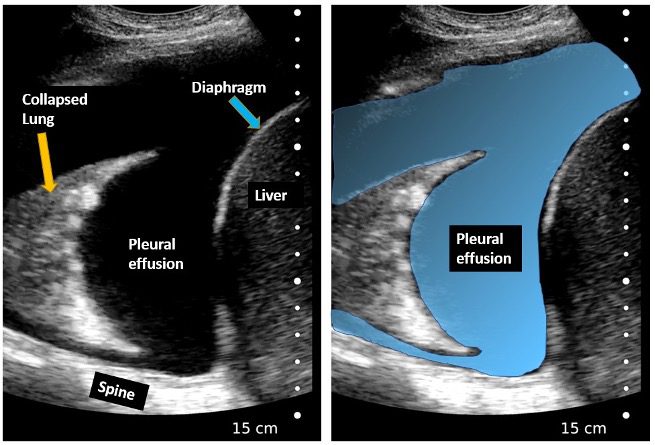

Figure 5. Right pleural effusion. Spine is seen superior to the diaphragm (Spine sign positive), Large anechoic pleural effusion seen. Right lung is collapsed (atelectasis).

- Pleural Effusion: Lung ultrasound is sensitive enough to identify even small effusions that may be missed on radiographs. Studies by Roch et al. (2005) and Yang et al. (1992) confirm its high diagnostic accuracy.